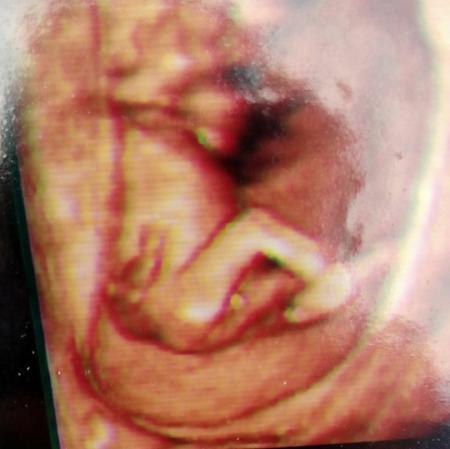

Hatte heute Feindiagnostik und alles in Ordnung. Baby ist zeitgerecht entwickelt und alle Organe sehen super aus. Und wir bekommen anscheinend doch ein Mädchen, letzte Woche hieß es noch 70% Junge. Aber denke da wächst nix mehr :-)

Bild zu Wollte euch mal berichten - Schwanger - wer noch? Rund um die Schwangerschaft

Sieht eindeutig nach Mädchen aus. Herzlichen Glückwunsch

Keine Frage…. Mädchen. Gratuliere und freue mich,dass alles gut ist. Cerclage sitzt gut?